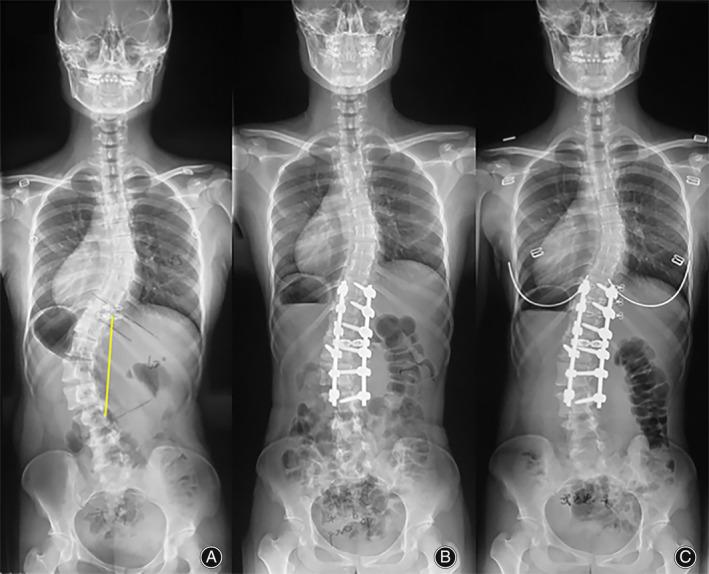

This is a retrospective radiographic study and Lenke 5C AIS patients undergoing SPF during the period from September 2017 to June 2021 were included. The modified S-line was defined as the line linking the centers of the concave-side pedicles of the upper end vertebra (UEV) and lower end vertebra (LEV) at baseline. A modified S-line tilt to the right is established as modified S-line+ (UEV being to the right of the LEV). The patients were further categorized into two groups: the Cobb to Cobb fusion group and the Cobb-1 to Cobb fusion group. Outcomes including thoracic Cobb angle, TL/L Cobb angle, coronal balance, upper instrumented vertebra (UIV) translation, lower instrumented vertebra (LIV) translation, UIV tilt, LIV tilt, LIV disc angle, thoracic apical vertebral translation, lumbar apical vertebral translation (L-AVT), L-T AVT ratio, L-T Cobb were measured at baseline, immediately after surgery, and the last follow-up. Radiographic parameters and the incidence of both proximal and distal decompensation between the two groups were compared by chi-square test.

Among 92 patients, 48 were modified S-line+ and 44 were modified S-line-. Modified S-line+ status was identified as a risk factor for postoperative proximal decompensation (p = 0.005) during follow-up. In Cobb to Cobb group, a higher occurrence of proximal decompensation in individuals with modified S-line+ status (p = 0.001) was confirmed. Also, in the Cobb to Cobb group with baseline modified S-line+ status, patients presenting decompensation showed a significantly larger baseline of the UIV tilt and postoperative disc angle below the lower instrumented vertebra. However, In Cobb-1 group, the incidence of decompensation after surgery showed no association with baseline modified S-line tilt status (p = 0.815 and 0.540, respectively).

The modified S-line could serve as an important parameter in surgical decision-making for Lenke 5C AIS patients. Cobb to Cobb SPF is not recommended with a modified S-line+ status, and the Cobb-1 to Cobb fusion may serve as a potential alternative.